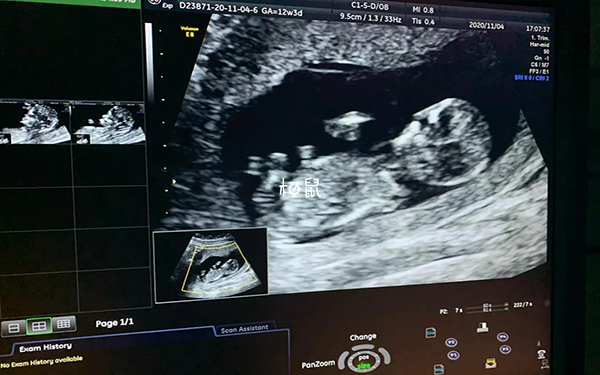

nt检查又称颈后透明带扫描,是通过检测胎儿颈项透明层厚度判断有无出现唐氏综合征的风险,是孕期一项非常重要的检查,进行NT检查后若发现NT值≥2.5mm,可能有唐氏综合征的风险存在,需要及时进行进一步检查,如羊水穿刺或绒毛活检等明确情况,若NT值<2.5mm,考虑是正常的,孕妇不必过度担心。

如果在nt检查过程中宝宝的胎动频繁、姿势变化多样,能完美配合医生进行检查,以至于检查得很快,而且是一次就通过了,则说明宝宝很活跃,暗示宝宝很健康,有着良好的神经系统发育,不过nt检查做的快也可能是因为宝宝胎位较好,不需要调整姿势就能快速的做完检查。

nt测量对宝宝位置会有一定的规定,胎儿部位不太好或头颈视角不合理都有可能会影响测量的准确度,所以对于医生来说,活跃的宝宝可以使医生更容易进行检查,并获得更准确的测量结果,所以如果在测量环节中胎儿部位不太好,超声医师有可能会要求孕妈妈活动后再次测量。